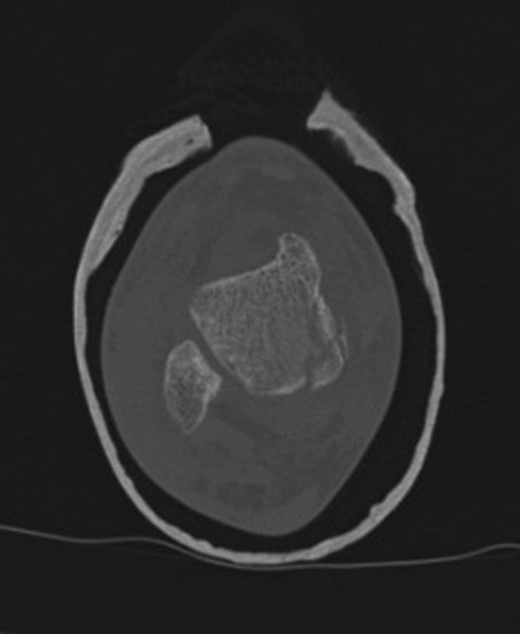

An otherwise fit and well 15-year-old Caucasian male patient, who was cycling down a hill, collided with an obstacle after being ejected over the handlebars of his pushbike. In the Emergency Department, the patient was appropriately triaged according to ATLS protocol which identified isolated closed injuries to his clavicle, and bilateral lower limbs, with no neurovascular compromise [2]. No head or neck injuries were sustained and a secondary survey revealed no other injuries other than some superficial abrasions. Plain radiographs revealed a left undisplaced clavicle fracture, an angulated extra-articular fracture of the left distal tibia and a right ankle talar tilt with no evidence of any bony fracture (Fig. 1). Initial management in the Emergency department included analgesia administration, a collar and cuff for his clavicle fracture and below knee plaster of Paris (POP) backslab for his bilateral lower limb injuries, with strict elevation and neurovascular monitor.

Right ankle plain radiograph demonstrating talar tilt and increased medial tibio-talar joint space.